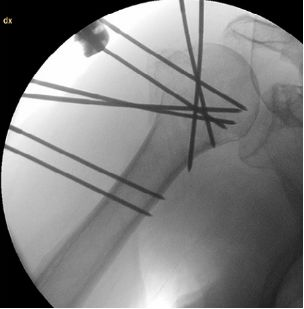

克氏针直径:2.5mm,全螺纹,结构如下图

典型病例:

62岁,男性

肱骨近端外展型位移骨折,伴内侧距骨折

通过“pins-bridging-fracture”外固定架技术固定